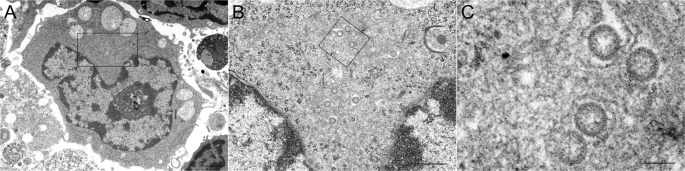

To confirm whether or not SFTSV was actually replicating in the antigen-positive cells, virions were observed by thin-section transmission electron microscopy. Virion particles were found in the vacuoles of the cytoplasm of the immunoblast-like cells in the necrotizing cervical LNs (Fig. 15). This morphology was similar to that observed in DH82 cells1. Taken together, these findings strongly indicate that SFTSV preferentially infects immature B cells.

Identification of viral particles in the spleen of fatal cat No. 2 by electron microscopy. (A–C) An electron microscopic analysis of the immunoblast-like cells in the cervical lymph node of the SFTSV-inoculated fatal cat (No. 2) at 8 dpi. (A) Round-shaped mononuclear cells are seen in the necrotizing lymphatic nodule that appear to be immunoblast cells. Virus-like particles 100 nm in diameter have moderately dense centers and are accumulated in the vacuoles of the immunoblast-like cells (B,C, higher magnification of A). Scale bars indicates 1 µm (A), 500 nm (B), 100 nm (C).